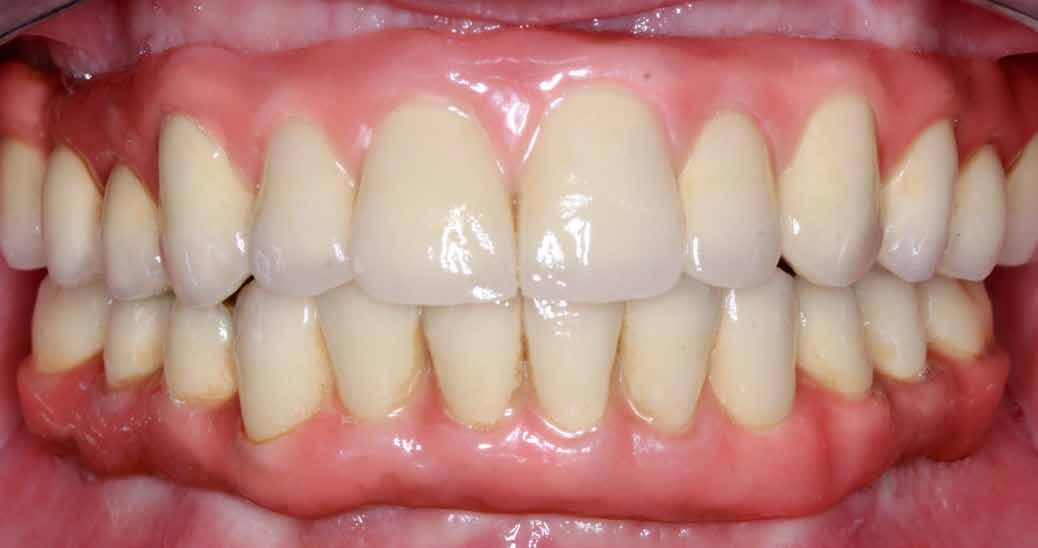

A fix fogszabályozó készülék mindössze 16 hónapos kezelés után került eltávolításra! Páciensünk legnagyobb örömére állcsontműtét nélkül sikerült mind az arcesztétikai, mind a funkcionális rehabilitáció (13–18. képek)